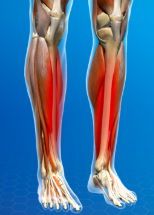

gastrocnemius, planterflex foot and flex knee

soleus, plantarflex feet

Shin splints also known as

Medial tibial stress syndrome

shin splints mechanism (6)

Pre planus, muscle imbalance/weakness, improper warmup, poor stretching, poor biomechanics, poor footwear

Sign/symptom of shin splints (3)

Distal shin pain, muscle weakness, anterior shin pain

Shin splints treatment

Ice, rest, NSAIDs, taping/padding foot, stretching/strengthening exercises, orthotics